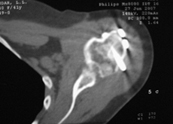

В момент осмотра: нормостеническая конституция, по передней поверхности плечевого сустава – рубец. Рука в положении приведения. Отведение не более 10 град, дальнейшие движения с лопаткой до 20-25 град. Амплитуда сгибания-разгибания 10-15 град. Ротация отсутствует. Пальпаторно - выраженная болезненность над суставом, особенно в проекции клювовидного отростка. При попытках пассивных движений – боль. Рентгенограммы и результаты КТ приложены(b2(3)_xr.jpg, b1(6)_ct.jpg).

Диагноз: неправильно сросшийся в условиях накостного остеосинтеза оскольчатый перелом головки левой плечевой кости (11-С3.2), асептический некроз головки плечевой кости, смешанная артро-миогенная контрактура левого плечевого сустава; демиелинизирующая нейропатия левого локтевого нерва.

Анализ ситуации позволяет считать, что основными причинами контрактуры являются неправильная репозиция фрагментов головки (разворот кверху и кзади), асептический некроз головки плечевой кости (отчетливое склерозирование на СТ).